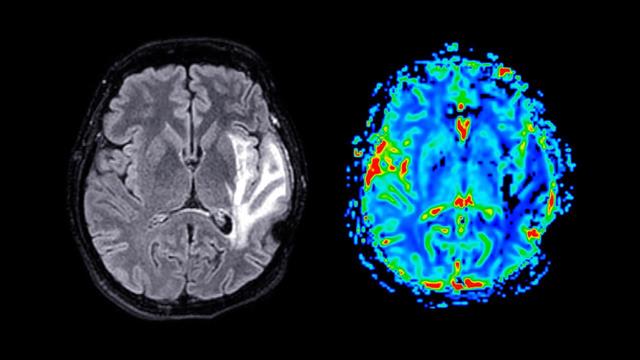

Επιλέχτηκαν 10.134 συμμετέχοντες 18 - 97, ετών οι οποίοι υποβλήθηκαν σε μαγνητική τομογραφία. Προηγουμένως συμπλήρωσαν ερωτηματολόγια. Ο καθένας έδωσε πληροφορίες για τον αριθμό πακέτων που κάπνιζε ημερησίως και τα χρόνια που κάπνιζε.

Με το δίκτυο FastSurfer ποσοτικοποιήθηκαν τα μεγέθη εγκεφάλων από 3D T1 απεικονιστικές εξετάσεις.